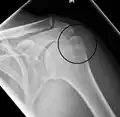

A spiral fracture of the distal one-third of the humerus shaft

A displaced supracondylar fracture in a child